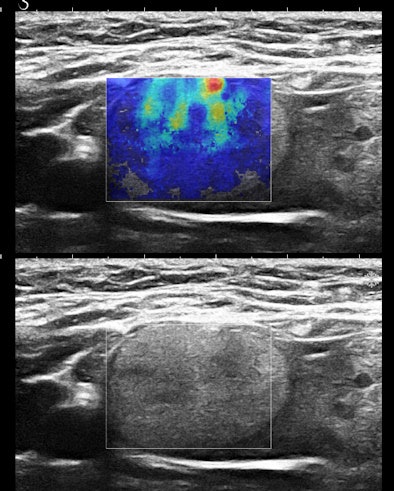

Figures 3A and 3B are the B-mode and simultaneous SWE of a follicular neoplasm of the thyroid. Notice how the elastogram indicates a cell population heterogeneity that is not visible in the original image.

![]() |

| Figures 3A and 3B. |

Homogeneous and heterogeneous are classic ultrasound image features. Perhaps ultimately, refining this descriptor and even quantifying it will be the most important role of SWE in practice.